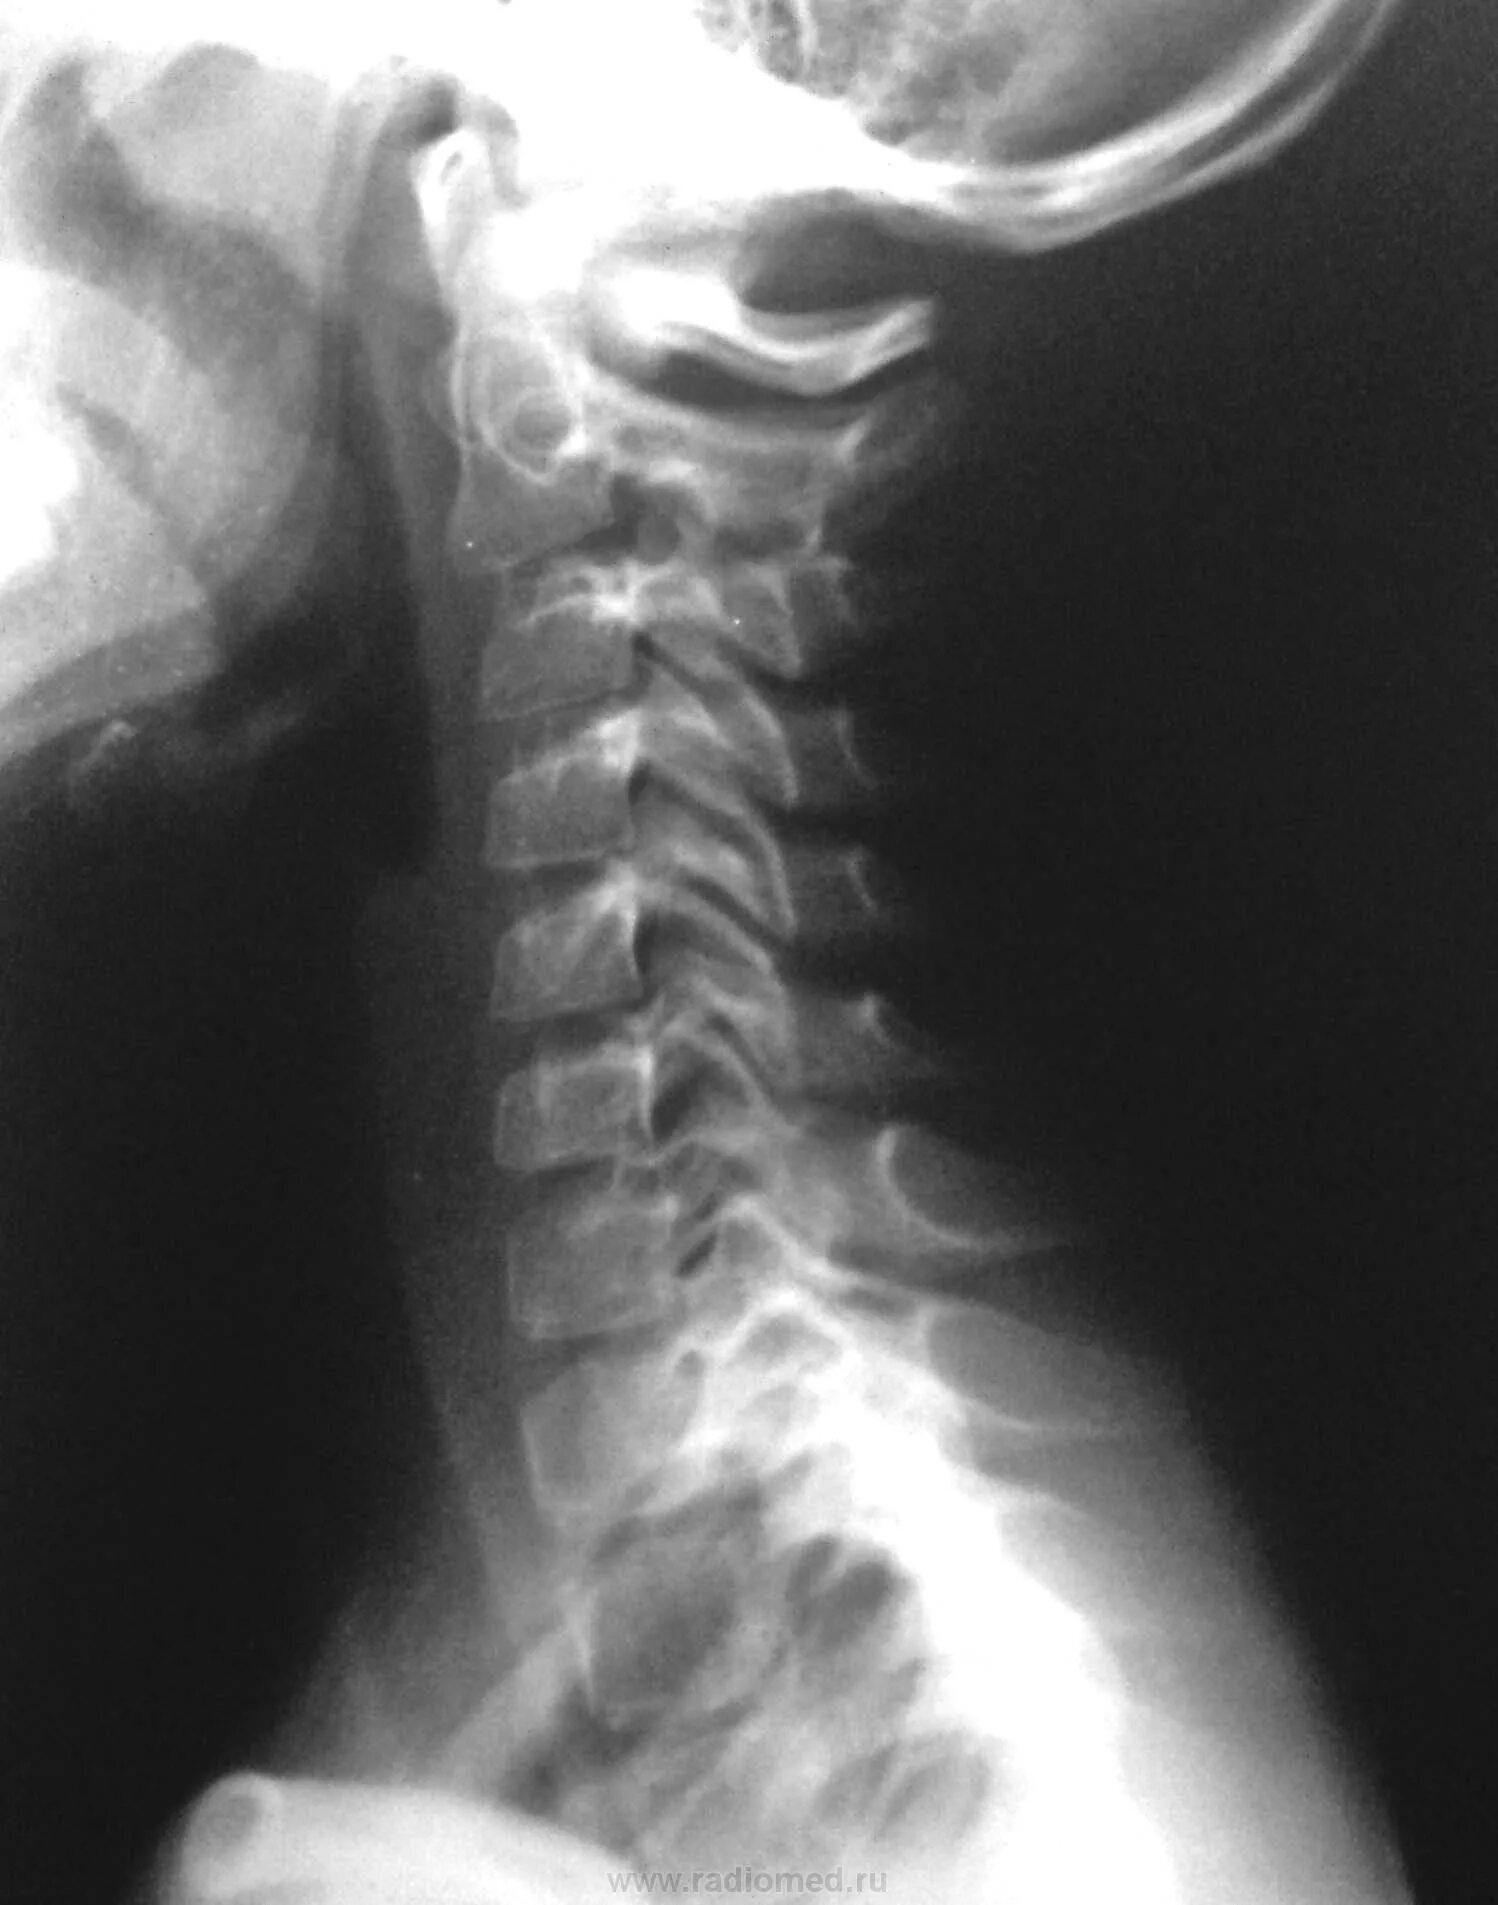

Подвывих по ковачу